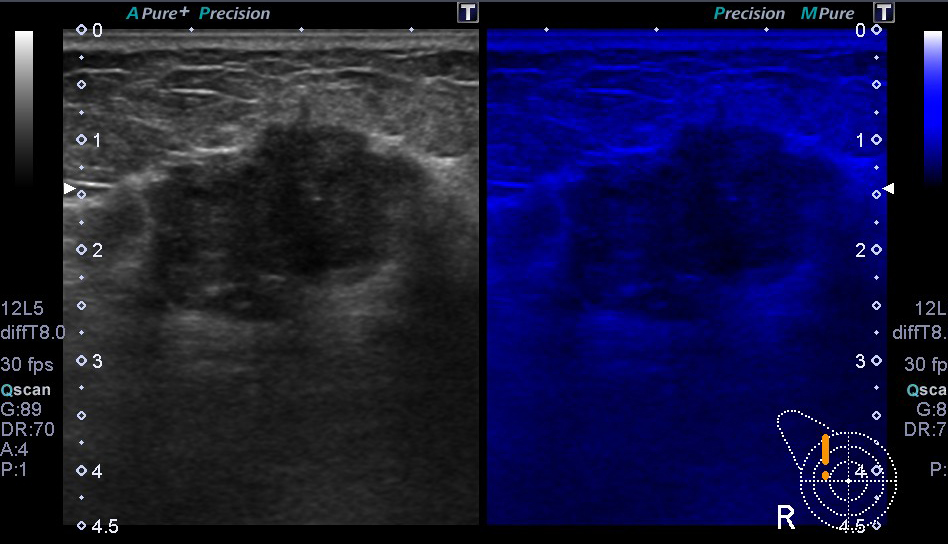

超音波(エコー) 診断画像

- 乳腺症

- 乳がん